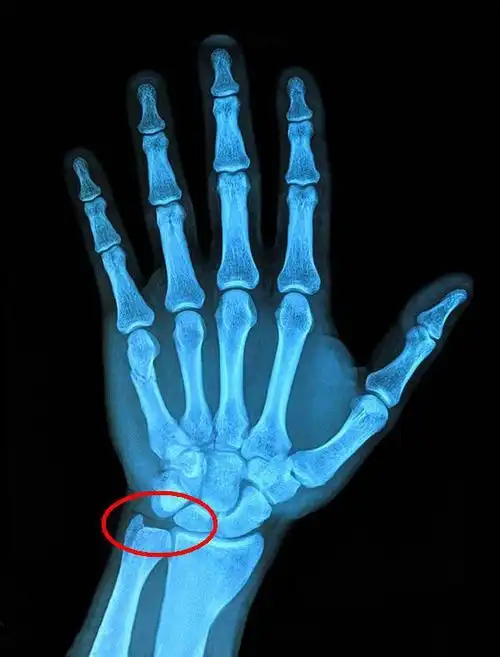

黑箭:舟骨腰部 白箭:舟骨滋养血管影9.桡骨茎突 10.尺骨茎突 11.

形成的椭圆形关节面,与桡骨腕关节面及尺骨下端的关节盘构成桡腕关节

左腕关节x线片左桡骨远端骨折并移位.

桡骨远端骨折